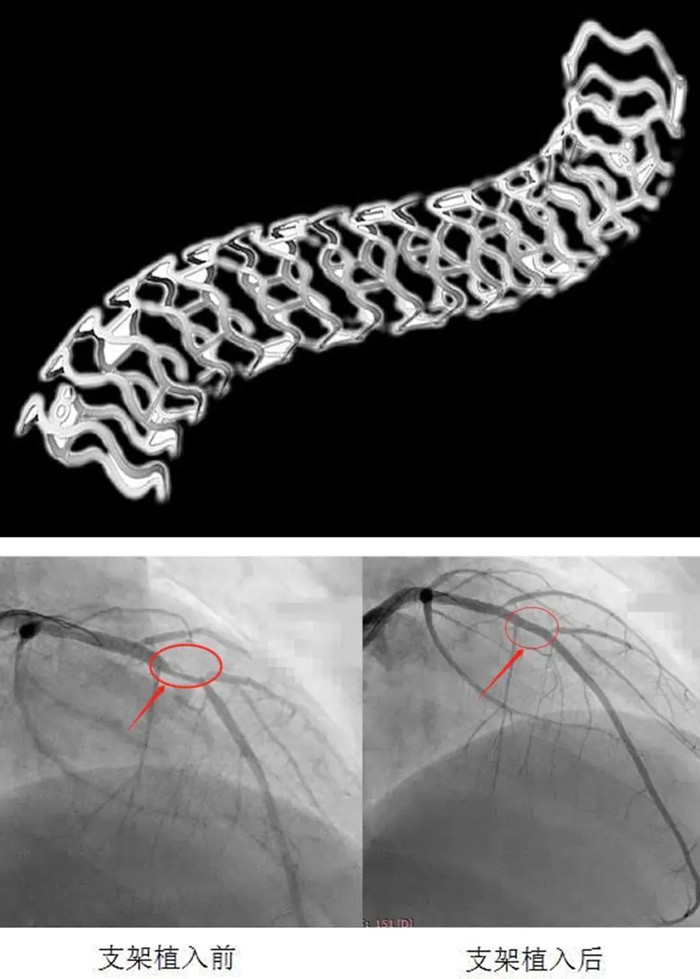

患者入院后完善術前準備,給予冠脈造影檢查示:右冠脈支架通暢,未見狹窄,左冠脈前降支近端可見90%局限性狹窄??紤]患者年輕,病變?yōu)锳型病變,參考患者家人意愿,決定給予患者可降解支架植入。

在郭明主任指導下,心內(nèi)科介入團隊先對病變處給予普通球囊及切割球囊充分預擴張,再給予血管內(nèi)超聲(IVUS)精確測量血管內(nèi)徑,選擇3.0×28生物可吸收支架,以8atm×30s釋放支架,再以血管內(nèi)超聲(IVUS)對支架貼壁情況給予評估后,以3.0后擴球囊給予“修飾”,IVUS再次評估,貼壁良好,手術順利結束。